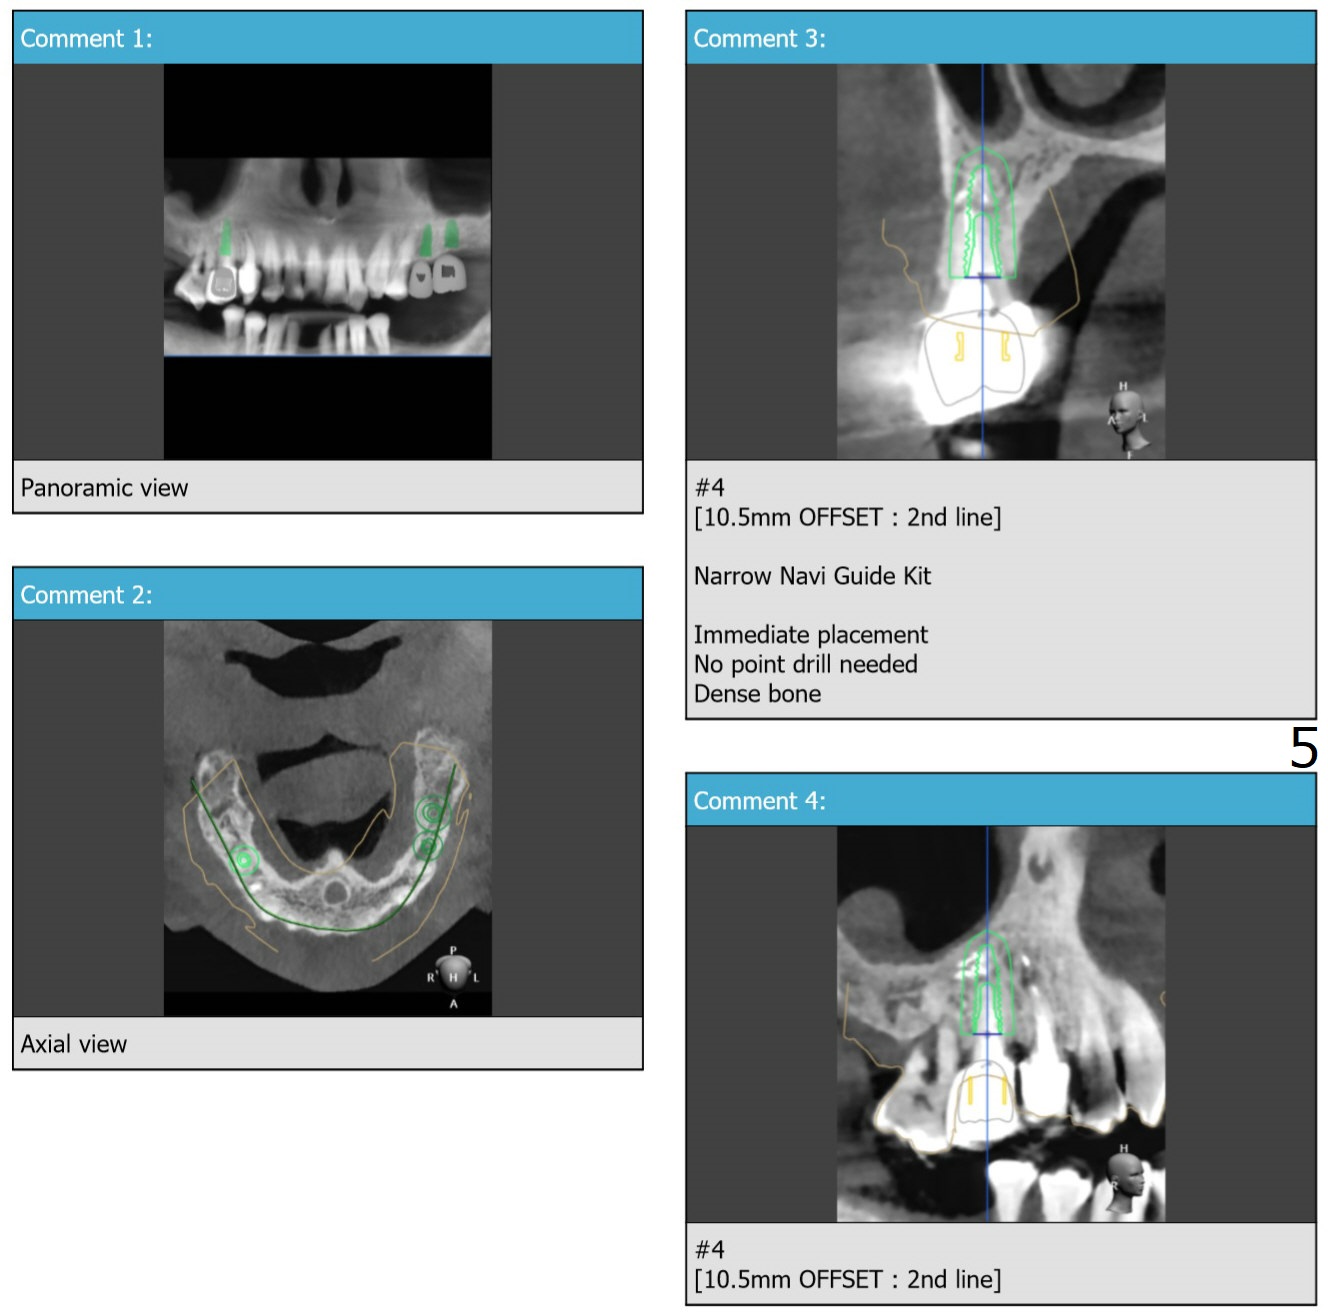

Compressive Necrosis

Return to No Deviation 矫正,糖尿病,种植水平

Xin Wei, DDS, PhD, MS 1st edition 03/19/2020, last revision 12/06/2020